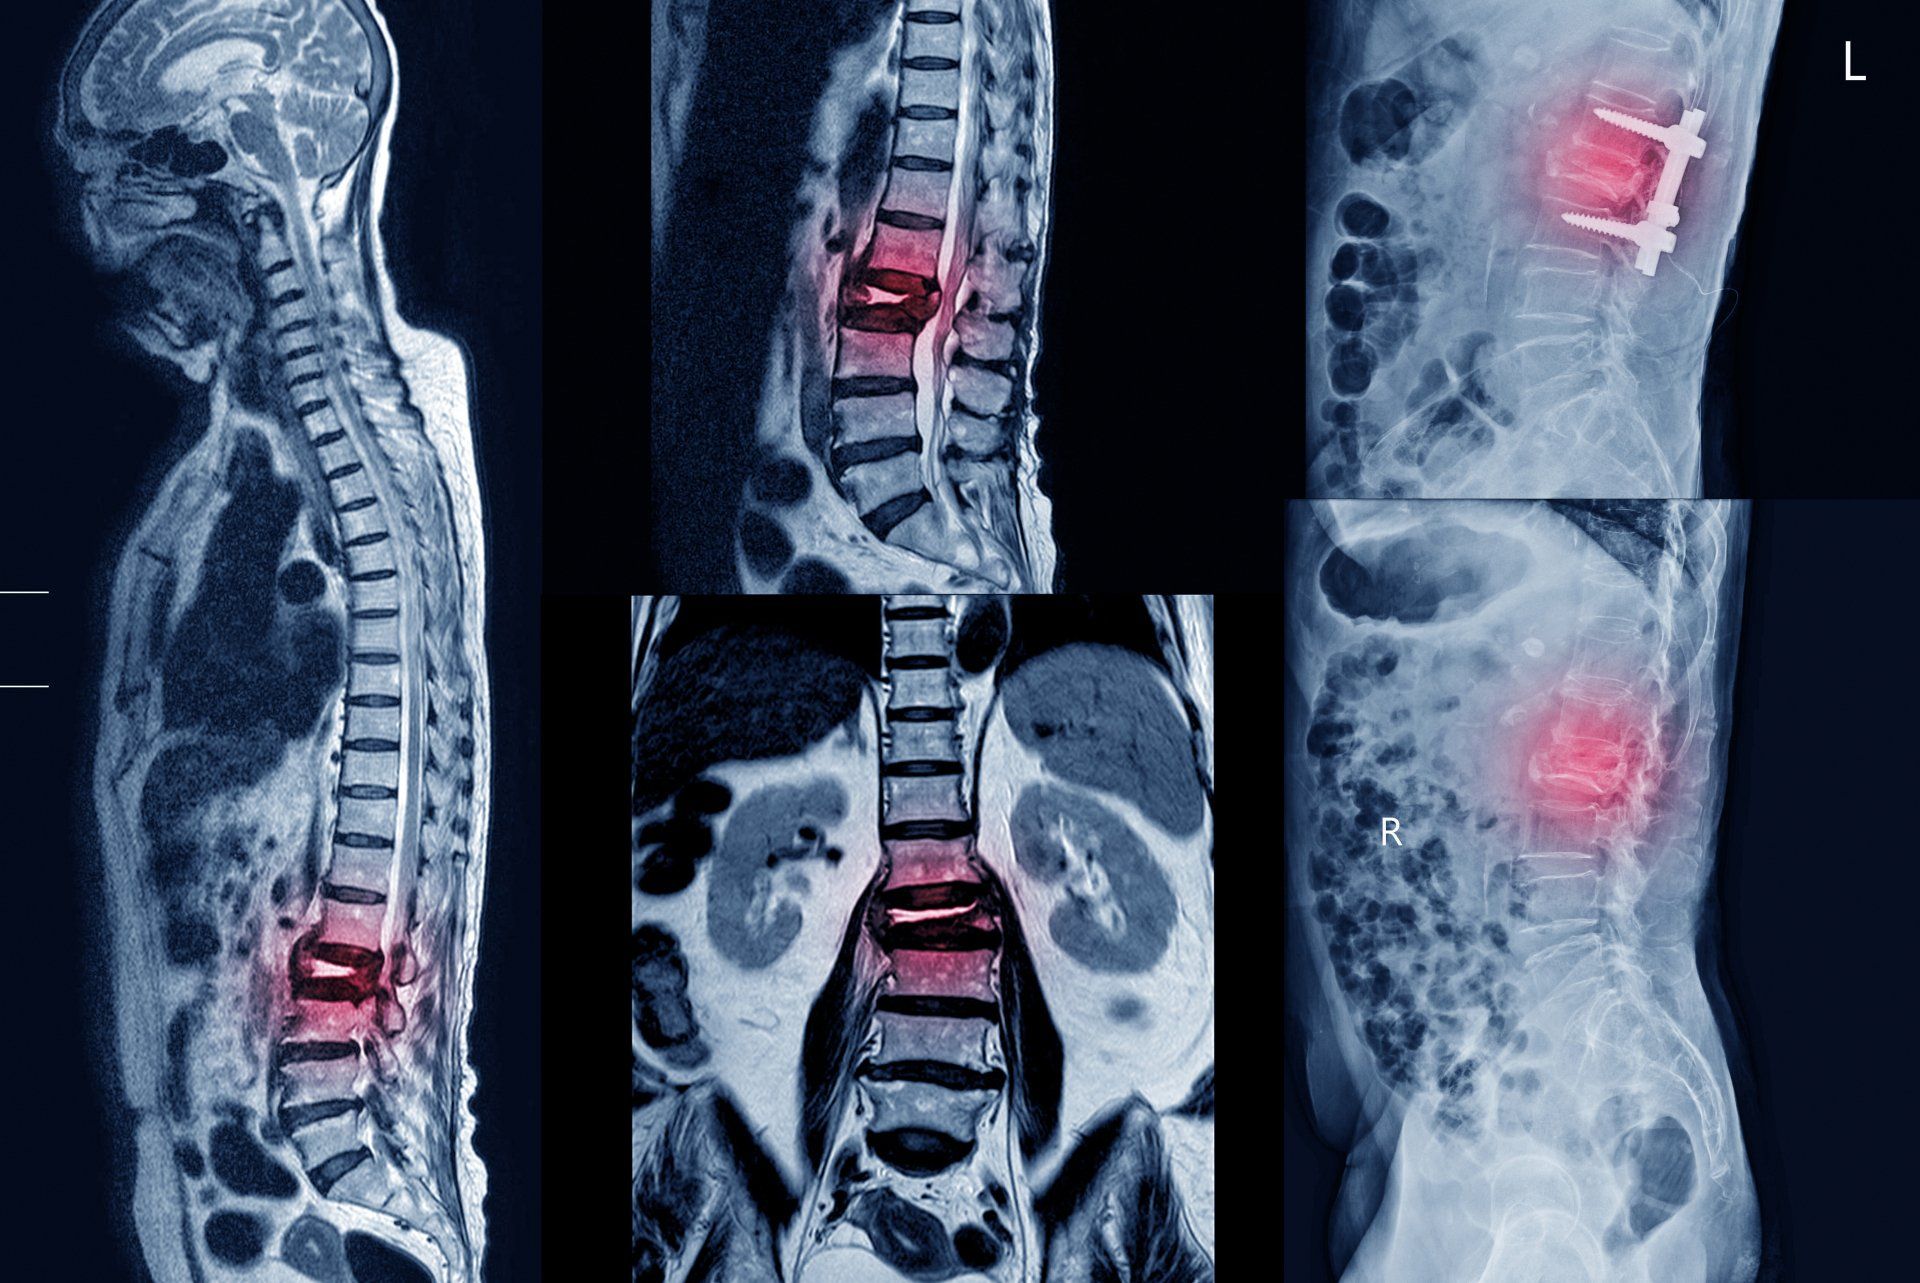

El dolor Irradiado muy común entre los pacientes de columna, se necesita un diagnóstico correcto para ir a la causa del mismo.

Cualquier compresión o tensión anormal de la raíz nerviosa debido a una protrusión, o incluso una hernia de disco cervical, u osteofitos en casos de espondilartrosis o espondilosis cervical, que reducen el diámetro del foramen intervertebral cervical; lesión postraumática, tras lesión por latigazo cervical, un hematoma postraumático o posquirúrgico, etc. pueden ser causa de una radiculopatía cervical.

Los discos herniados son una de las causas más comunes de radiculopatía lumbar. Los discos herniados paramedianos (la forma más común) provocan la compresión de la raíz nerviosa que cruza hacia abajo, al nivel del receso lateral del canal espinal. En caso de hernia de disco lateral, foraminal o extraforaminal, la raíz nerviosa superior (saliente) se ve afectada. Muy a menudo, el cuadro clínico proporciona suficiente información sobre la raíz nerviosa afectada. Además, la estenosis de canal y la estenosis foraminal también causan síndromes radiculares. En este caso, los cambios osteocondríticos y espondilóticos degenerativos conducen a un estrechamiento del canal espinal. Más raramente, tumores espinales o procesos inflamatorios, como por ejemplo espondilodiscitis, son la causa de radiculopatías lumbares. En caso de osteoporosis conocida o tras un traumatismo, también es siempre recomendable considerar las fracturas vertebrales como parte

del diagnóstico diferencial.